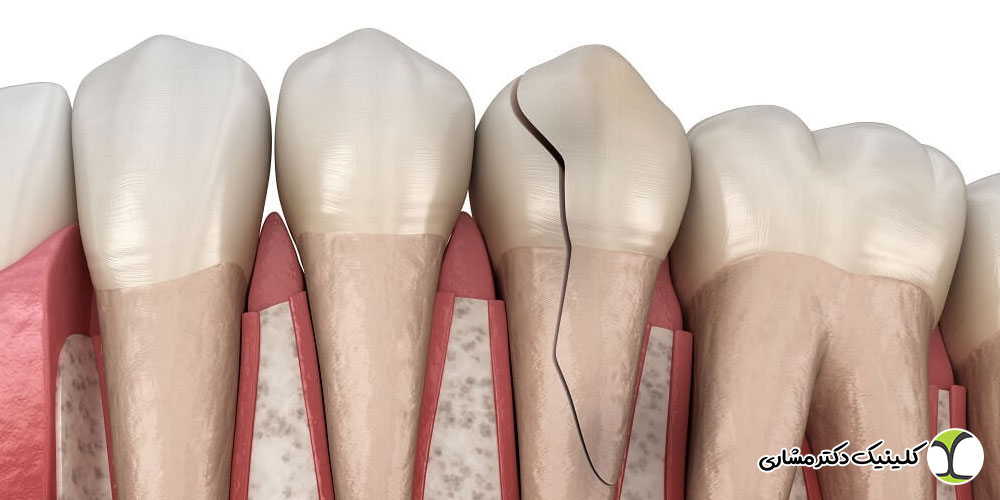

ترک یا شکستگی دندان

ترکهای ریز و گاهی نامرئی در دندان میتوانند مسیر ورود باکتریها به پالپ را فراهم کنند. این ترکها ممکن است در اثر جویدن غذاهای سخت، دندانقروچه یا ترمیمهای نامناسب ایجاد شوند. در صورت نفوذ باکتریها، التهاب و عفونت پالپ رخ داده و در نهایت مرگ دندان اتفاق میافتد.